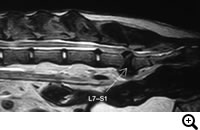

馬尾症候群

症状:背部痛、慢性的な後肢跛行、後肢の爪先をひきずる、段差の上り下りを嫌うなど

馬尾症候群とは

腰仙椎領域で肥厚した椎間板の線維輪などによって、神経根が圧迫されている状態です。痛みや神経症状をともないます。

診断

レントゲン検査、脊髄造影検査、CT検査、MRI検査

治療

Dorsalnectomyという腰仙椎に窓をつくり、神経根の圧迫を取り除く手術などをおこないます。